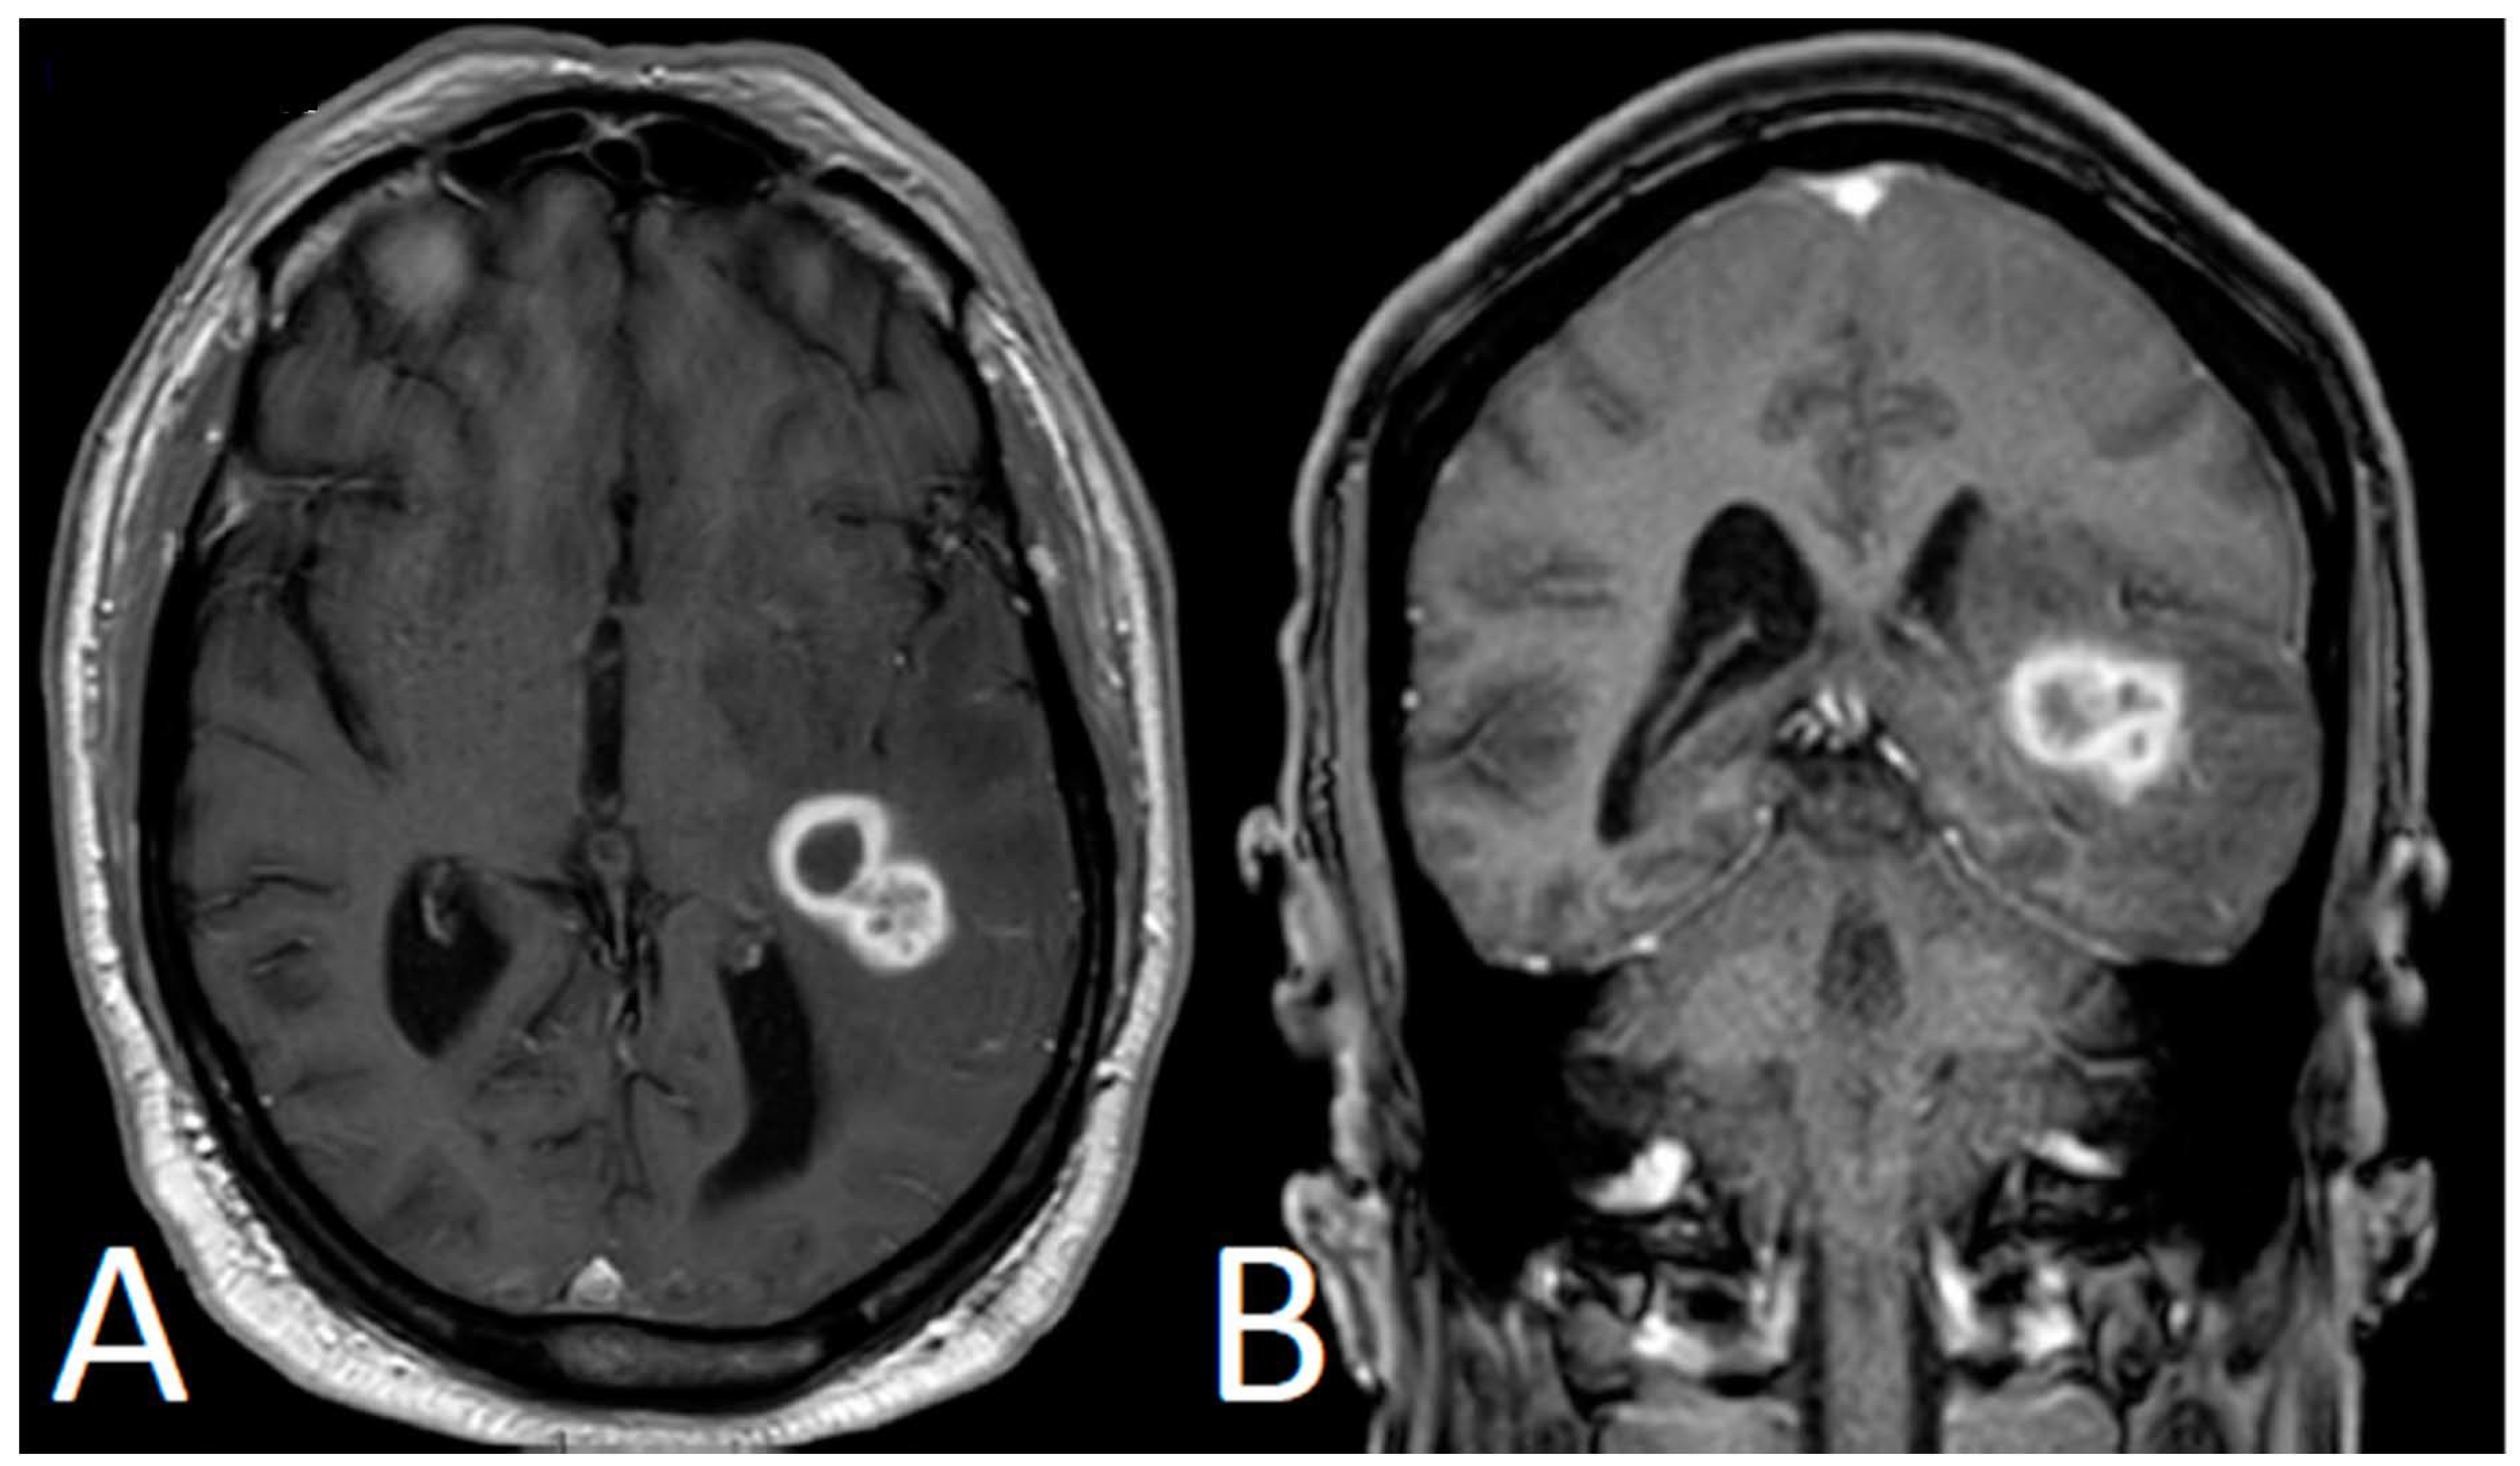

Cerebral Invasive Aspergillosis in a Case of Chronic Lymphocytic Leukemia with Bruton Tyrosine Kinase Inhibitor